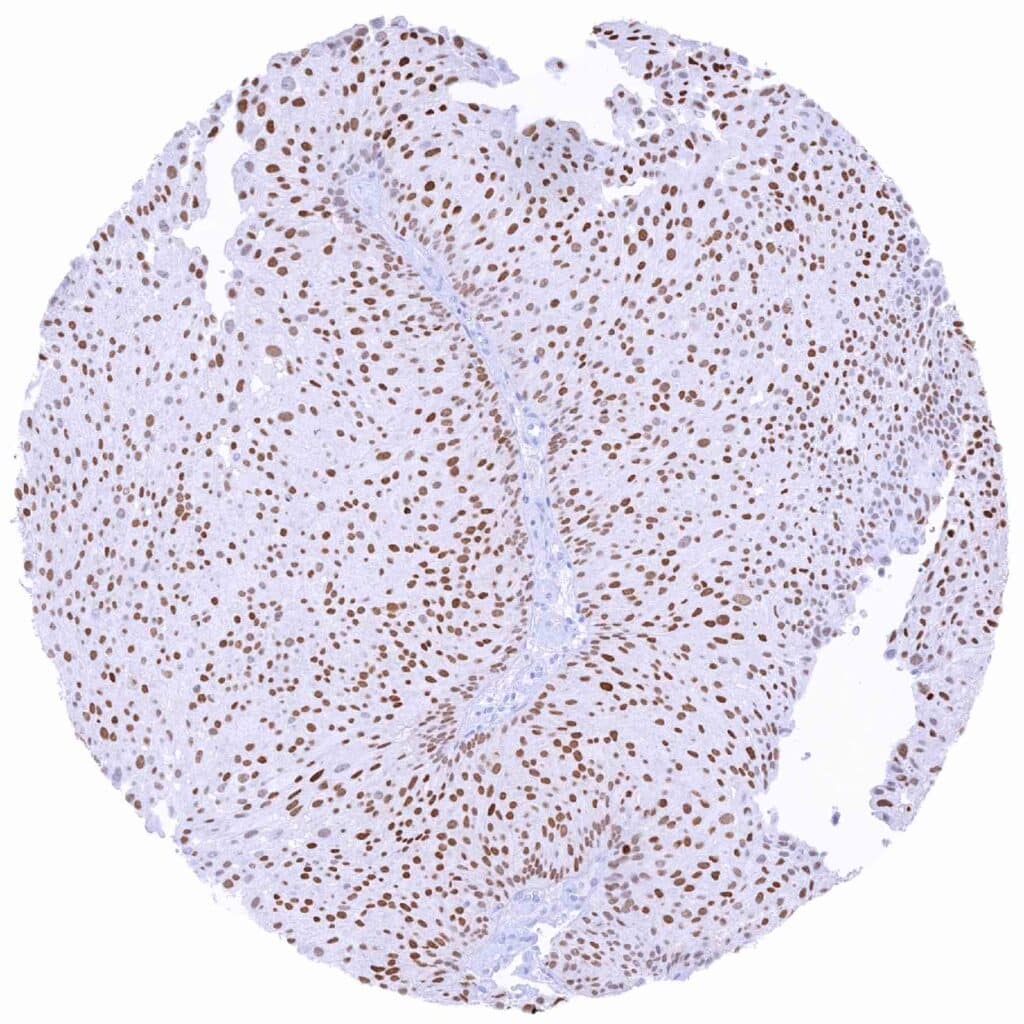

Thyroid – Papillary cancer with strong PAX8 immunostaining of tumor cells